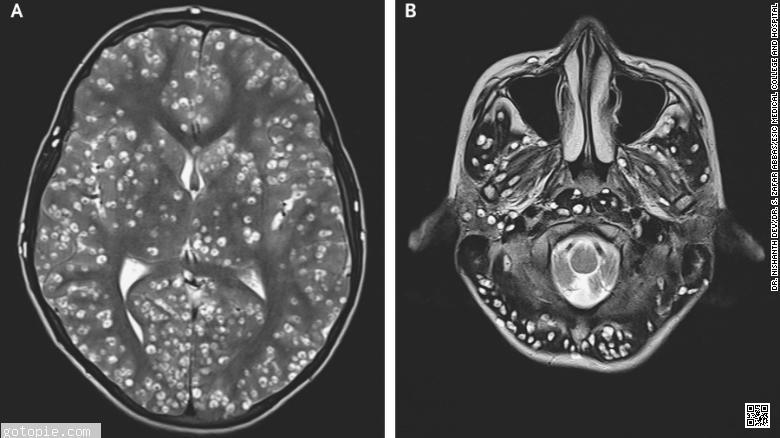

为了进一步了解他的病情,医护人员进行了核磁共振检查,发现他的大脑皮层(大脑组织的外层)以及脑干(包括位于脊髓上方头部后部的小脑)中的囊肿造成了损伤。 诊断:神经囊尾蚴病,一种由某人吞下绦虫卵而引起的脑部寄生虫病,绦虫卵已通过肠道绦虫的粪便。幼虫爬出卵,进入肌肉和脑组织,在那里形成囊肿。 医生还发现病人右眼和右睾丸有囊肿。 由于囊肿的数量和位置,他的医生决定不给这位年轻人服用抗寄生虫药物。这些会恶化脑出血和炎症,同时导致失明。相反,给患者服用了抗炎药地塞米松和抗癫痫药物。 到达急诊室两周后,病人死亡。 据美国疾病控制和预防中心称,囊尾蚴病感染在全世界范围内都有发生,尽管这些人体的寄生入侵大多发生在发展中国家的农村地区,那里允许猪出没,卫生设施也很差。 虽然这些感染在猪与人类粪便没有接触的国家中可能很少见,但囊虫病可以在世界任何地方获得,包括美国和其他西方国家。 症状取决于囊肿的位置;有时,肿块在皮肤下形成,有时,困惑是大脑发生损伤的唯一迹象。 症状可能出现在感染数月甚至数年后,通常是当囊肿开始死亡,导致组织肿胀。 一般来说,这些感染需要抗寄生虫药物和消炎药物的结合,但如果病人没有反应或减少脑肿胀,手术可能是必要的。即使瘫痪性感染本身不再需要注意或治疗,症状也可能需要护理。 囊尾蚴病患者不能将其疾病传播给其他人;只有肠道内感染绦虫的人才能在缺乏或忽视适当的卫生条件时传播可能危及生命的卵。 |